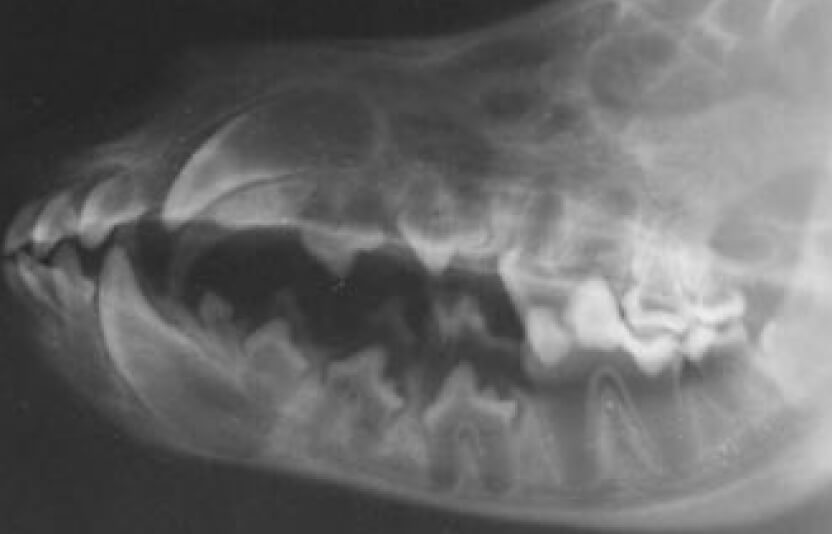

Схема или снимок зубов собаки

Зубы собаки